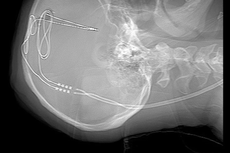

La cirugía es parte de un ensayo clínico realizado por el Instituto de Neurociencia Rockefeller de la Universidad de West Virginia e implica la implantación de pequeños electrodos que envían pulsos eléctricos a la parte del cerebro que recompensa las conductas de búsqueda de placer.

El método se conoce como estimulación cerebral profunda (DBS) y se ha utilizado anteriormente para tratar con éxito los síntomas de la enfermedad de Parkinson, al cambiar la forma en que funciona el centro de recompensa del cerebro.

El presidente ejecutivo del Instituto de Neurociencia Rockefeller, el Dr. Ali Rezai, dijo a NBC News que la estimulación cerebral profunda se había utilizado con éxito para tratar los síntomas de la enfermedad de Parkinson durante décadas.

"Nuestra hipótesis era que al usar la estimulación cerebral profunda en esta parte del cerebro, estaríamos esencialmente normalizando los niveles de dopamina", dijo el Dr. Rezai.